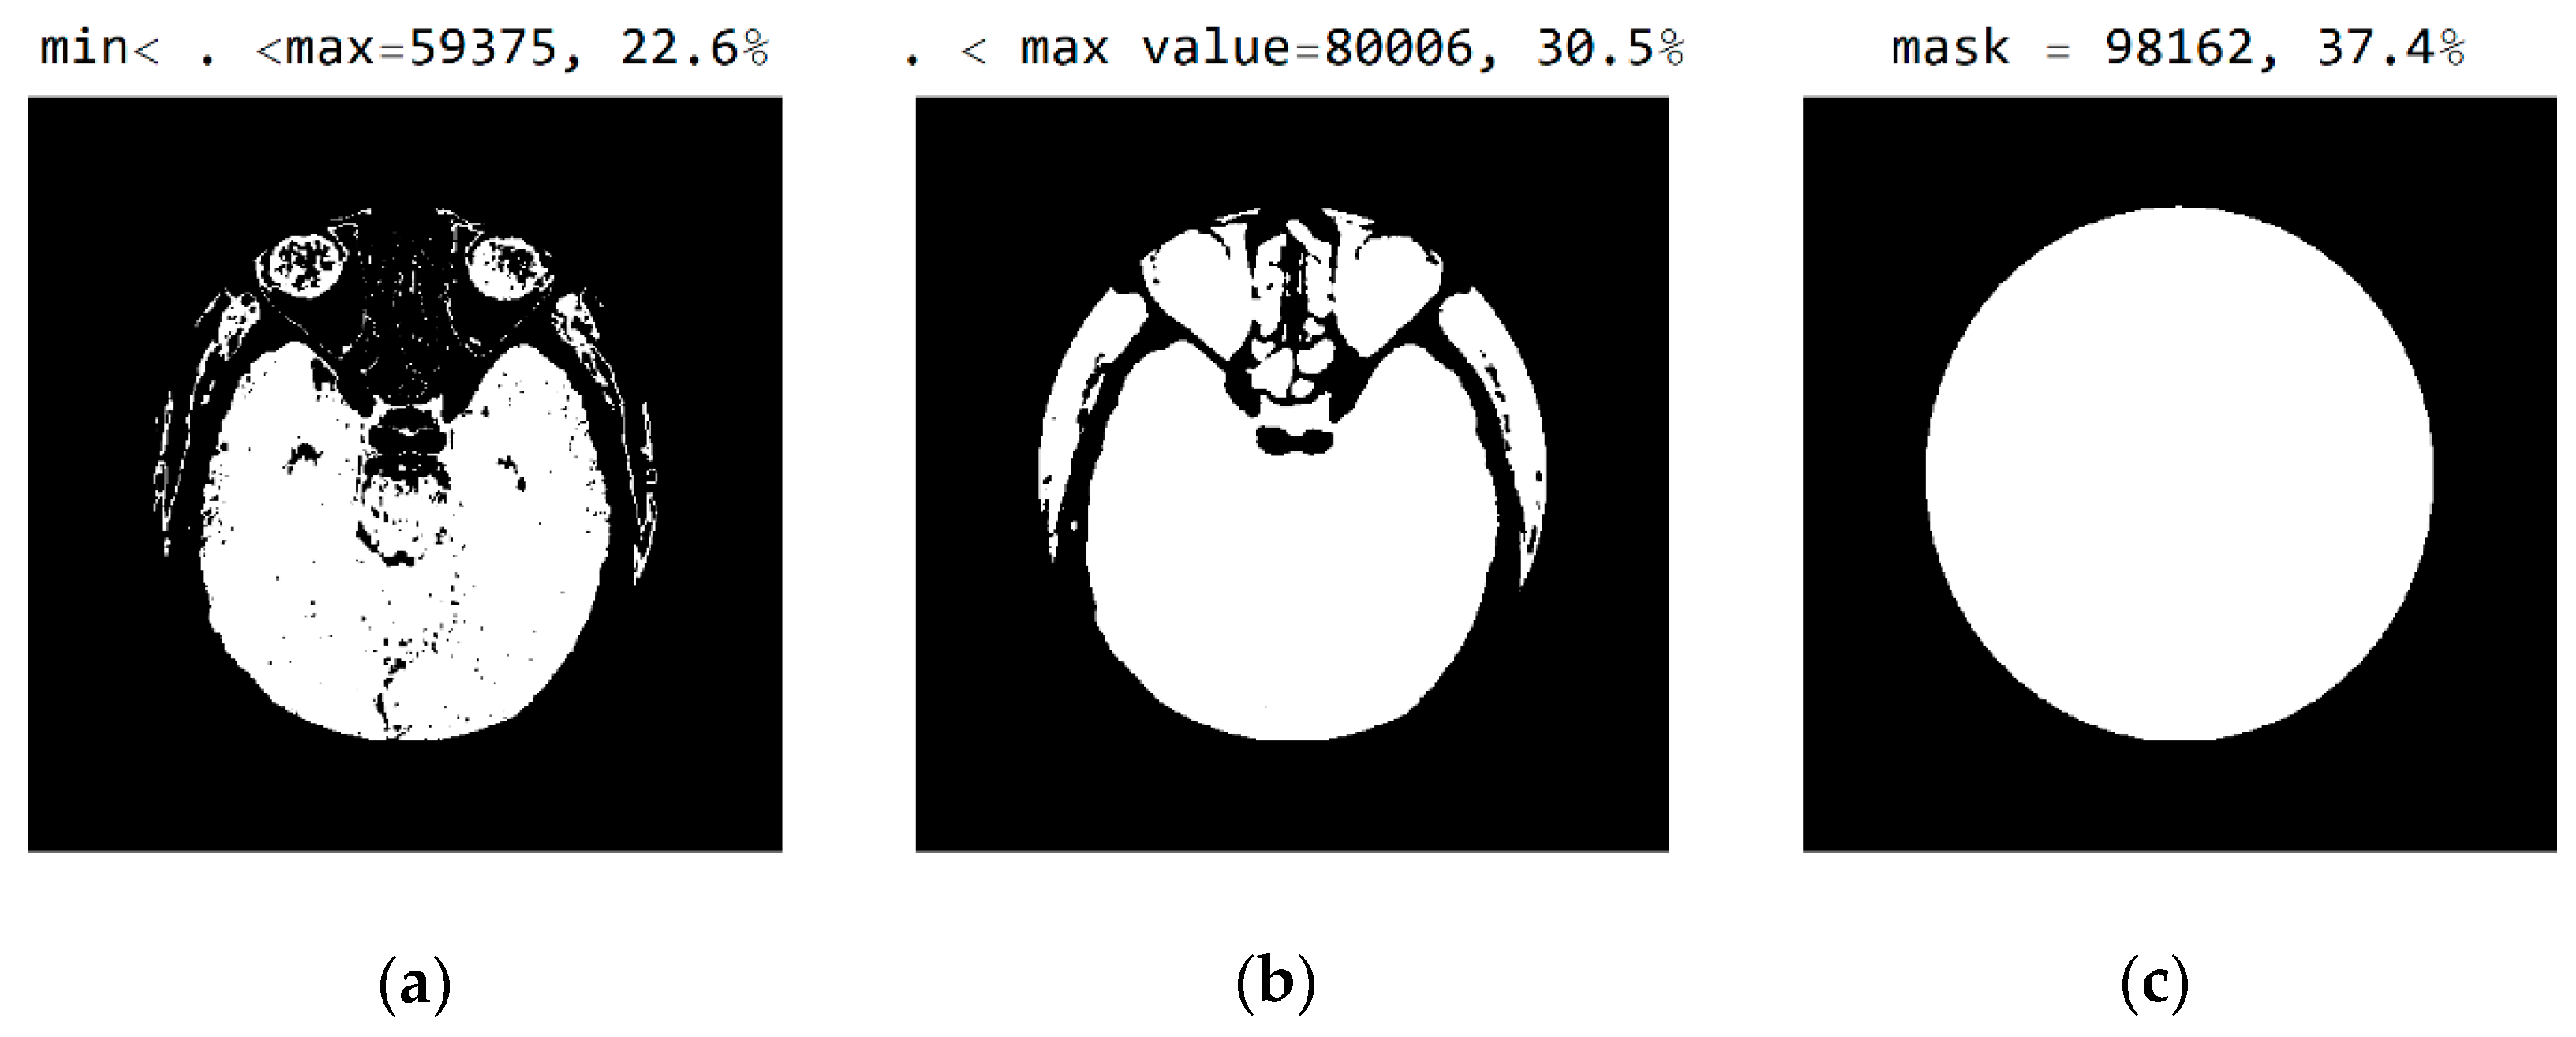

2.2. Smart Visualization Method (SVMI)

3.1. Technological Description